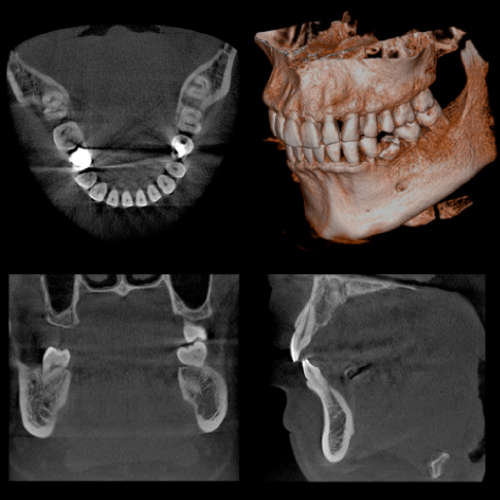

口腔外科治療とCT

親知らずや、埋伏歯の診断に利用することで、立体的に歯の位置や、顎骨の状態、周囲の神経や血管の管との関係を明確に診断できます。 それにより治療の安全性が高まり、患者様にとっても有益となります。のう胞や腫瘍に関しては、その位置や大きさなどを立体的に確認でき、その後の治療計画、処置に役立ちます。顎関節症、歯性上顎洞炎などの疾患に関しても、今までのレントゲンでは得られなかった情報を得れることで診査診断、治療に多く貢献できます。